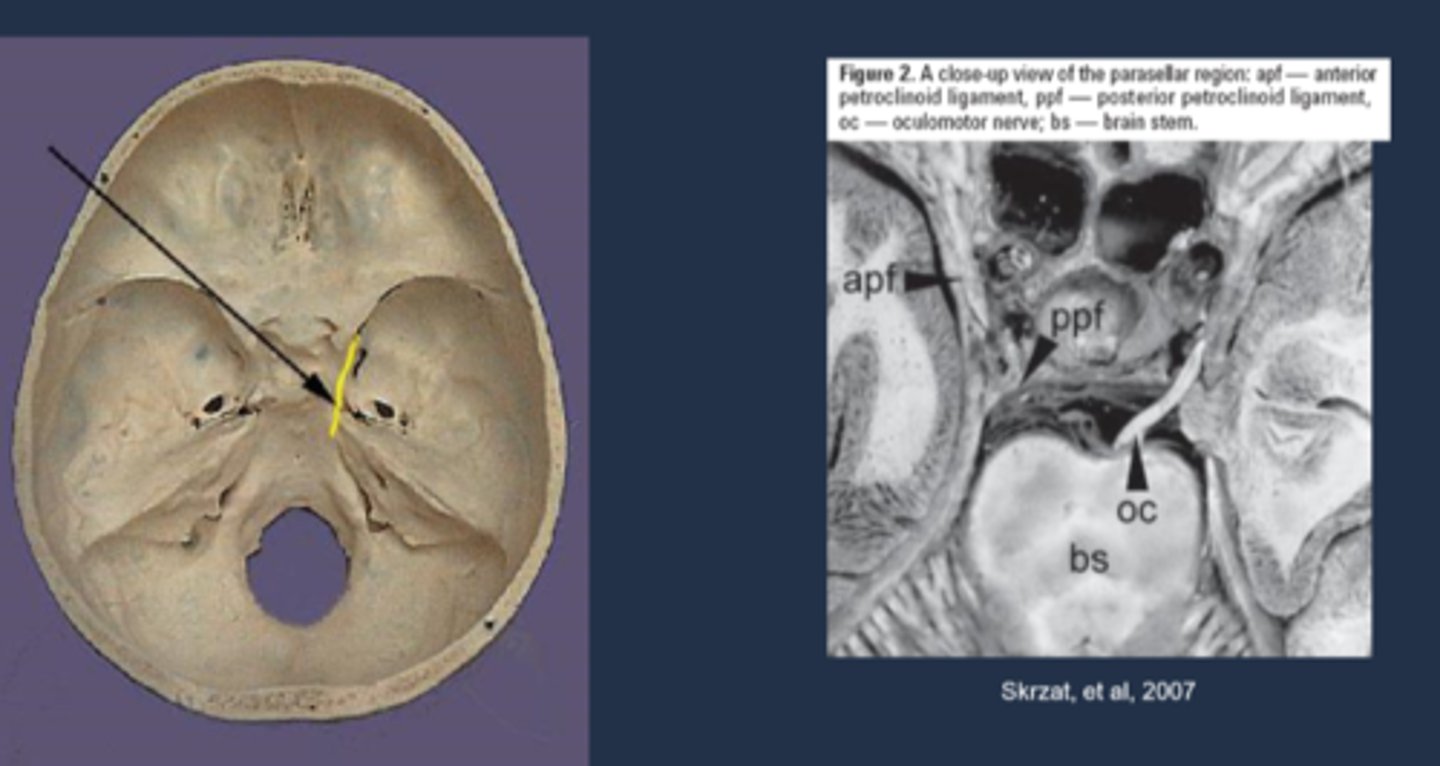

uncas of parahippocampal gyrus (inferior area of temporal lobe) = lateral to the brainstem = lateral to CN III in brainstem

Explain how the Uncal region can affect CN III in Uncal syndrome.

CN III leaves brainstem = pupillomotor fibers move dorsomedially = uncus herniates = compresses CN III dorsomedially against petroclinoid ligament and dorsum sellae = pupil is blown